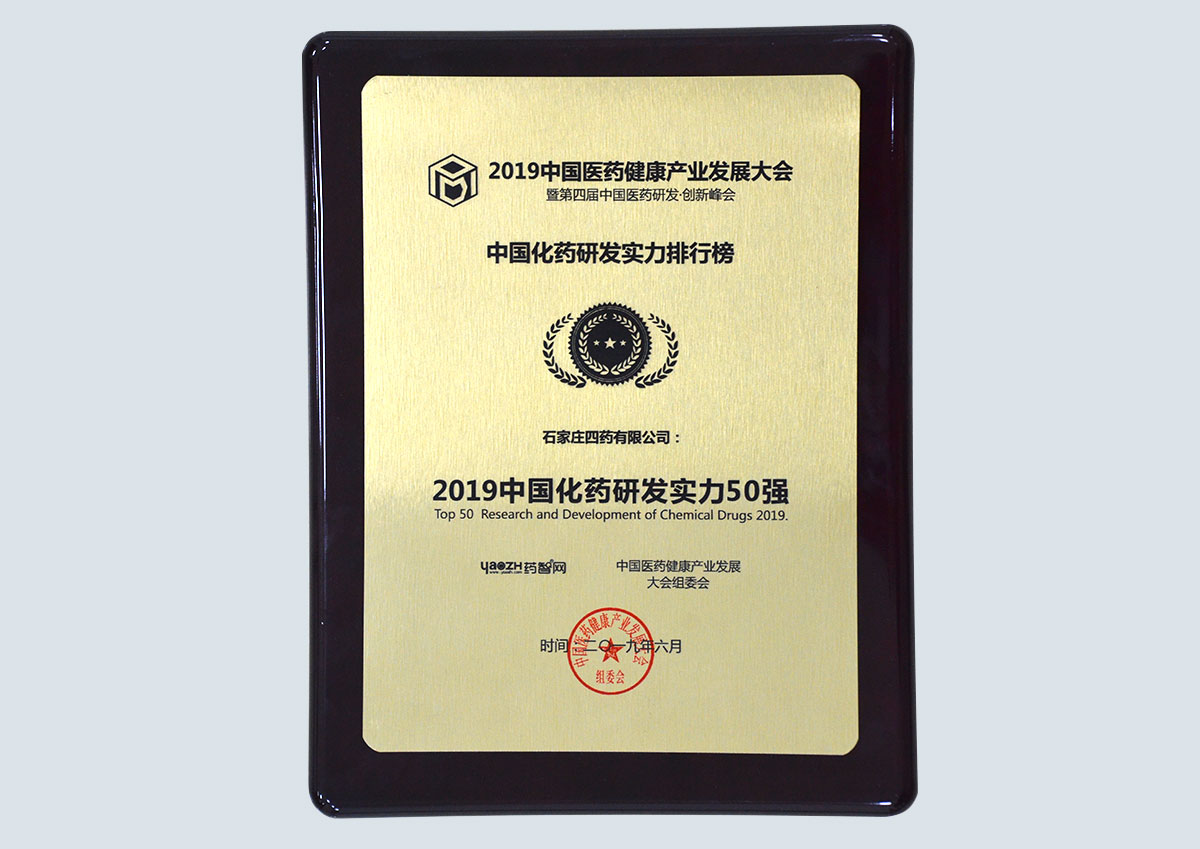

专利证书